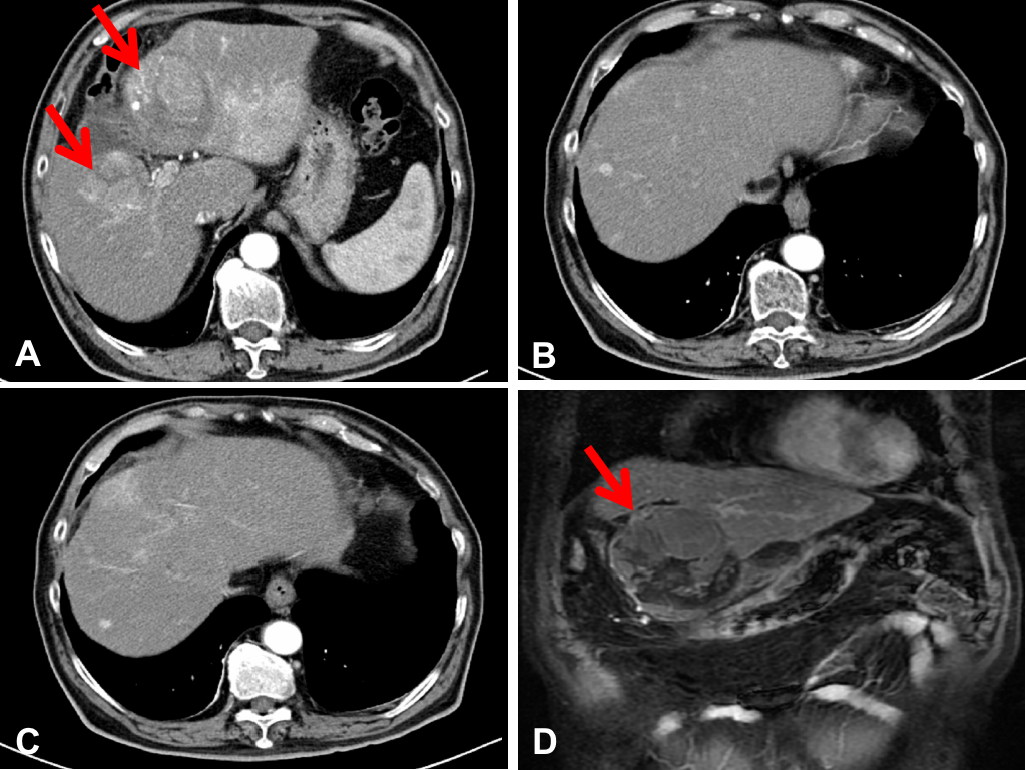

病例简介患者女性,46,因体检发现肝占位1周,于2019年2月就诊于浙江大学医学院附属第二医院。7年前因左乳腺肿物于外院行左乳腺癌改良根治术,术后未行放化疗。&n...